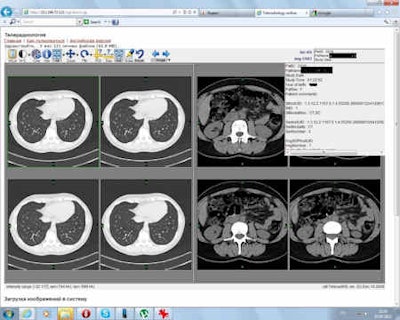

Practicing teleradiology in Russia. Image courtesy of Dr. Elena Mershina.

The Russian Federal Rehabilitation Center launched its own teleradiology portal.Fortunately, things are starting to change in busy and technologically advanced hospitals where large patient flows put quality and optimal service above personal insecurities. Business brings discipline. For example, the Russia Federal Rehabilitation Center launched its own teleradiology portal (see image above), where any radiologists and patients can upload and view their DICOM images and get a professional second opinion.3 The Russian Federal Emergency Medicine Center in St. Petersburg actively experiments with lightweight teleradiology clients, including their use with satellites and robots. Educated and cost-aware Russian patients represent another driving force behind teleradiology: Flying from Vladivostok to Moscow for an expert opinion takes the same amount of time and money as flying to Boston or Tel-Aviv, making the patients extremely interested in remote image interpretation and the substantial savings it offers (not to mention saving lives).